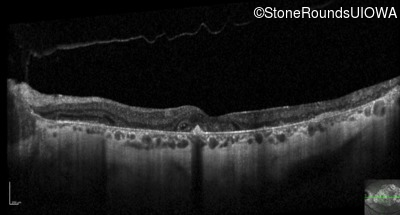

Optical Coherence Tomography - Left - 20/32 -2

Exemplar / OCT Stack

OCT Stack